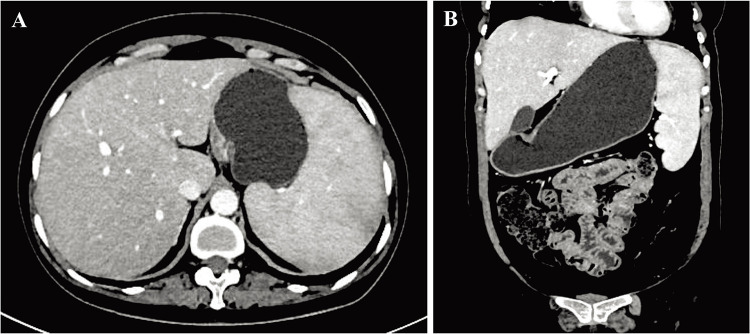

Case presentation: We reported the case of a 49-year-old female patient who was diagnosed with pSS according to dry mouth, dry eyes, splenomegaly, multiple positive autoantibodies, positive Schirmer's test and biopsy of labial gland with decreased number of acini and focal lymphocytic infiltration. Due to hematological involvement and liver dysfunction repeatedly, the pSS patient was admitted to the hospital and treated with glucocorticoids, immunosuppressants and hepatoprotective drugs. However, the pancytopenia failed to improve. Considering pancytopenia of the pSS patient caused by massive splenomegaly, splenectomy was recommended to the patient. The hematological involvement was significantly improved after splenectomy. Besides, another 46-year-old woman with a similar clinical manifestation was diagnosed with pSS complicated by massive splenomegaly, however, the patient refused to undergo the splenectomy.